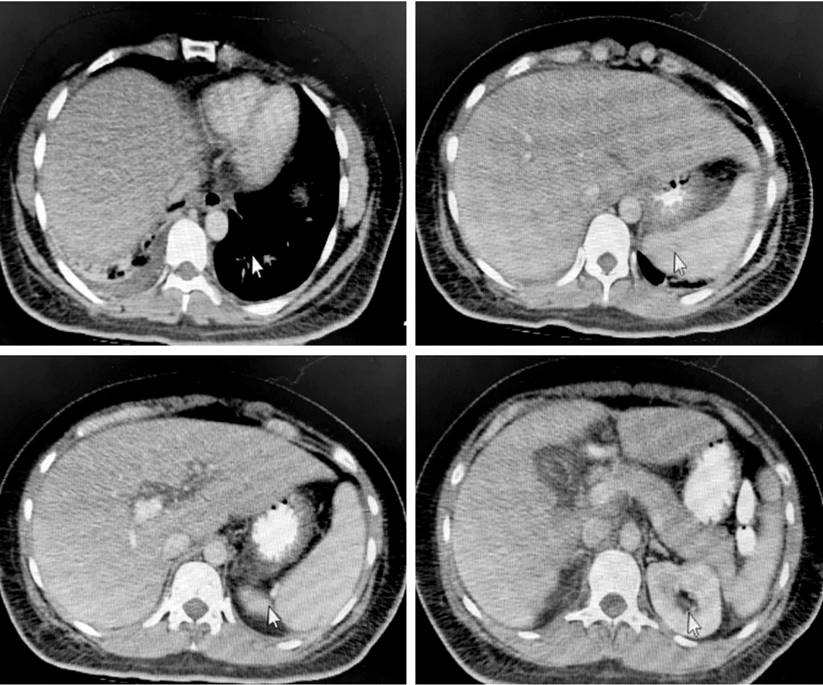

After the liver and bile duct ultrasound, hepatic steatosis, cholecystitis, and biliary sludge were detected. Consequently, the surgeons assessed the patient and requested both abdominal tomography (Figure 1) and magnetic resonance cholangiopancreatography (Figure 2). However, as hyperbilirubinemia persisted at the expense of direct hyperbilirubinemia, gastroenterologists performed an endoscopic retrograde cholangiopancreatography (ERCP). The ERCP revealed the papilla of Vater in the second flat duodenal portion, selective admission to the bile duct with bow papillotome plus hydrophilic guide. In addition, the contrast-enhanced cholangiography confirmed a normal caliber bile duct without stones, exploration of the bile duct with Dormia basket and extraction of biliary sludge and retained bile, and bile duct washing until clear bile drainage.